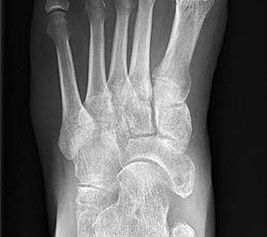

Stehende Aufnahmen des Fußes dorsoplantar (dp) und seitlich sowie des OSG anteroposterior (ap) sind die Grundlage der konventionellen Röntgendiagnostik (Abb. 5). Ergänzend werden gelegentlich die Rückfuβ-Alignement Aufnahme nach Saltzman 19 und Vergleichsaufnahmen der Gegenseite durchgeführt.

Der Talo-Metatarsale I Winkel bzw. die laterale talonaviculare Subluxation auf der stehenden dorsoplantaren Aufnahme des Fuβes dokumentieren das Ausmaβ des Vorfuβ abductus (Abb. 6 a,b). Ein dp Talo-Metatarsale I Winkel von > 10° (nach medial konvex) ist als pathologisch anzusehen. Mit der Bestimmung der talocalcanearen Divergenz (Abb. 6 c) erhält man ein Eindruck über das Ausmaβ des Rückfuβ valgus; eine leichte Divergenz bis ca. 12° gilt als physiologisch 20.

Auf der seitlichen, stehenden Aufnahme des Fußes wird ebenfalls der laterale Talo-Metatarsale I Winkel (Abb. 6 d) gemessen und so das kollabierte mediale Längsgewölbe dokumentiert. Auch hier gilt ein Talo-Metatarsale I Winkel von > 5° (nach plantar konvex) als pathologisch 21. Der Kollaps findet dabei meist im Talonaviculargelenk, seltener in der Naviculocuneiform-Gelenkreihe statt. Instabilität und Arthrose im 1. TMT sollten ausgeschlossen oder bei der Operationsplanung mit einbezogen werden. Weitere wichtige radiologische Messungen zur Beurteilung der Planovalgus-Statik und Progression der Deformität sind der laterale talo-calcaneare Winkel (Abb. 6 e) und der Abstand des Os cuneiforme-Unterrandes zum Untergrund (Abb. 6 f, Cuneiform height, 22. Eine anteriore Translation des Talus auf dem Kalkaneus findet man sowohl auf der ap, als auch auf der seitlichen Aufnahme des Fuβes mit Aufhebung der Cima-Linie.